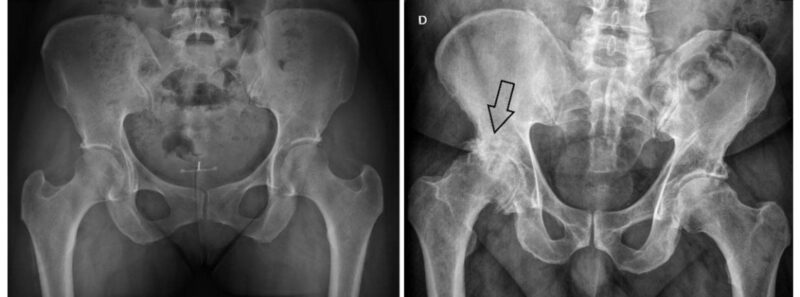

artrose do quadril

A artrose é descrita como uma doença degenerativa progressiva com consequências negativas na qualidade de vida e na recuperação cirúrgica.

A prótese total de quadril é apresentada como uma cirurgia extremamente eficaz, com altos índices de satisfação e melhora significativa, mas o texto ressalta que os resultados são melhores quando realizada no momento certo, evitando o adiamento.